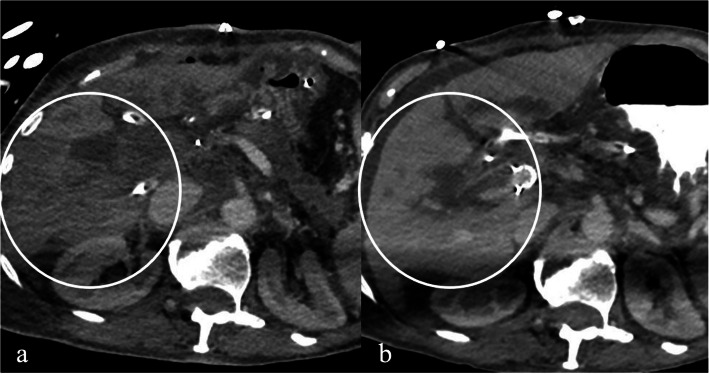

Case presentation: A 78-year-old female developed portal vein high grade stenosis after resection of an ampullary cholangiocarcinoma. The patient presented with acute liver failure and impaired coagulation function. Imaging confirmed transient ischemic changes of the hepatic parenchyma. Salvage attempt with a portal venous stent was decided to prevent irreversible liver damage. The procedure was successful with a satisfactory clinical outcome.